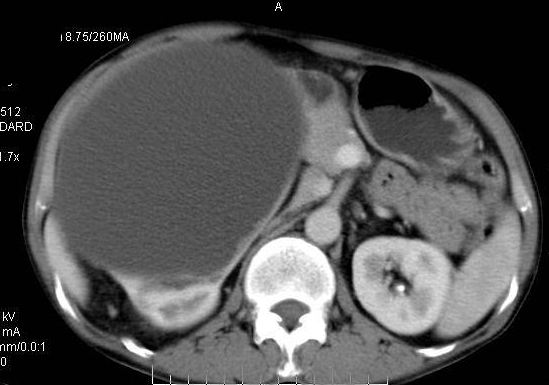

男性 60岁,腹部肿块4年余,肿块逐渐增大,活动性差,无血尿。

平扫

定位;肾明显与病灶杯口相交,可以肯定病变来自右肾。

定性;病灶囊性为主,前下部含实性成分,及钙化,部分壁厚薄不均。

肾囊实性病变有;1,囊性肾癌2,囊性肾瘤。3,复杂囊肿。4,重复肾伴积水。然2、3壁相对规则。

综上考虑;囊性肾癌》重复肾伴积水。